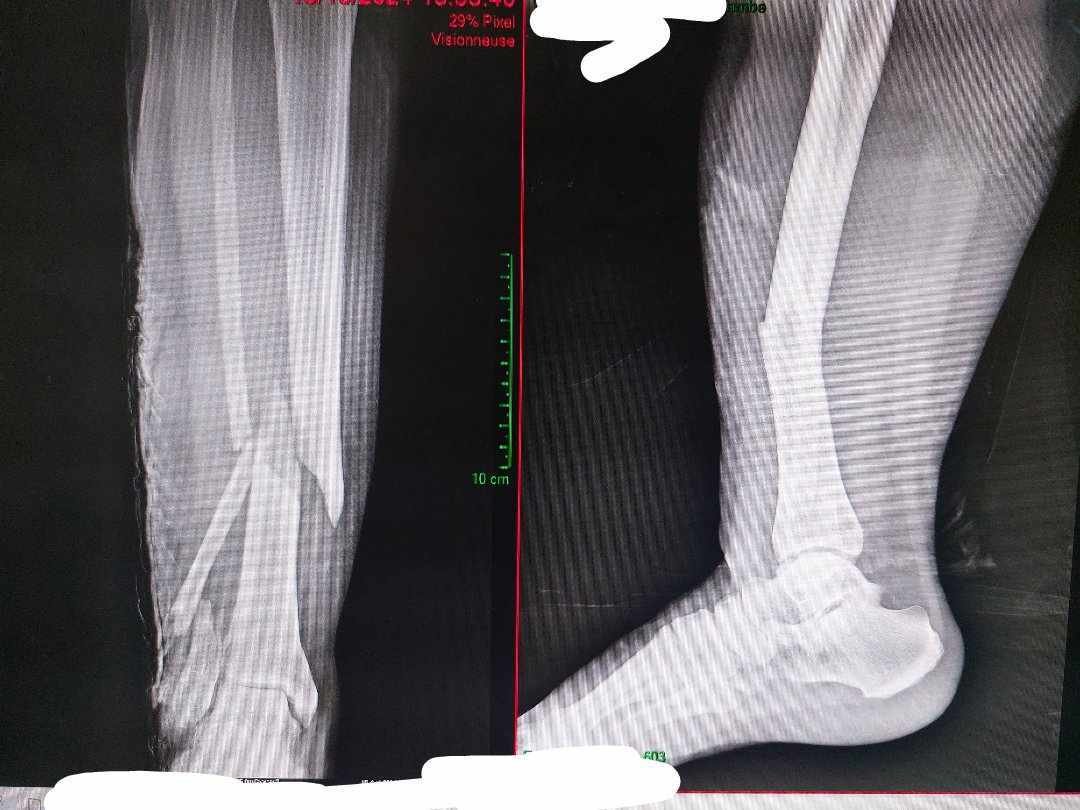

J'ai eu une patiente en syndrome catatonique, schizophrène en rupture de traitement, avec une fracture ouverte de tibia suite à une histoire un peu floue.

Normalement les fractures de tibia sont parmis les plus douloureuses, et la elle avait une bifocale de fibula + tibia distal ouverte.

Habituellement on les réduit + immobilisation en attente de bloc sous propofol au déchoc aux urgences tellement c'est douloureux. La je l'ai immobilisé sans aucun antalgique, la patiente n'a même pas levé un sourcil. Aucun mouvement de son corps. C'était absolument dingue.

Pendant l'opération les anesth ont mis deux fois moins d'antalgiques et d'anesthésiants aussi